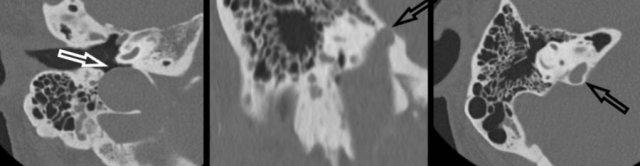

Di căn tăng sinh mạch hoặc u màng não

Các tổn thương xương tăng sinh mạch, như u máu xương, u màng não nền sọ, mô bào Langerhans, hoặc di căn xương, đã được mô tả là những nguyên nhân có thể gây ù tai theo nhịp mạch.

Bên trái là hình ảnh u màng não trên MRI.

Hình ảnh chuỗi xung T1W có tiêm thuốc tương phản từ trục ngang.

Khối ngấm thuốc nằm ở góc tiểu não-cầu não bên trái với phần kéo dài vào ống thần kinh hạ thiệt (mũi tên), mảnh tĩnh mạch cảnh (vòng tròn) và tai giữa (đầu mũi tên).